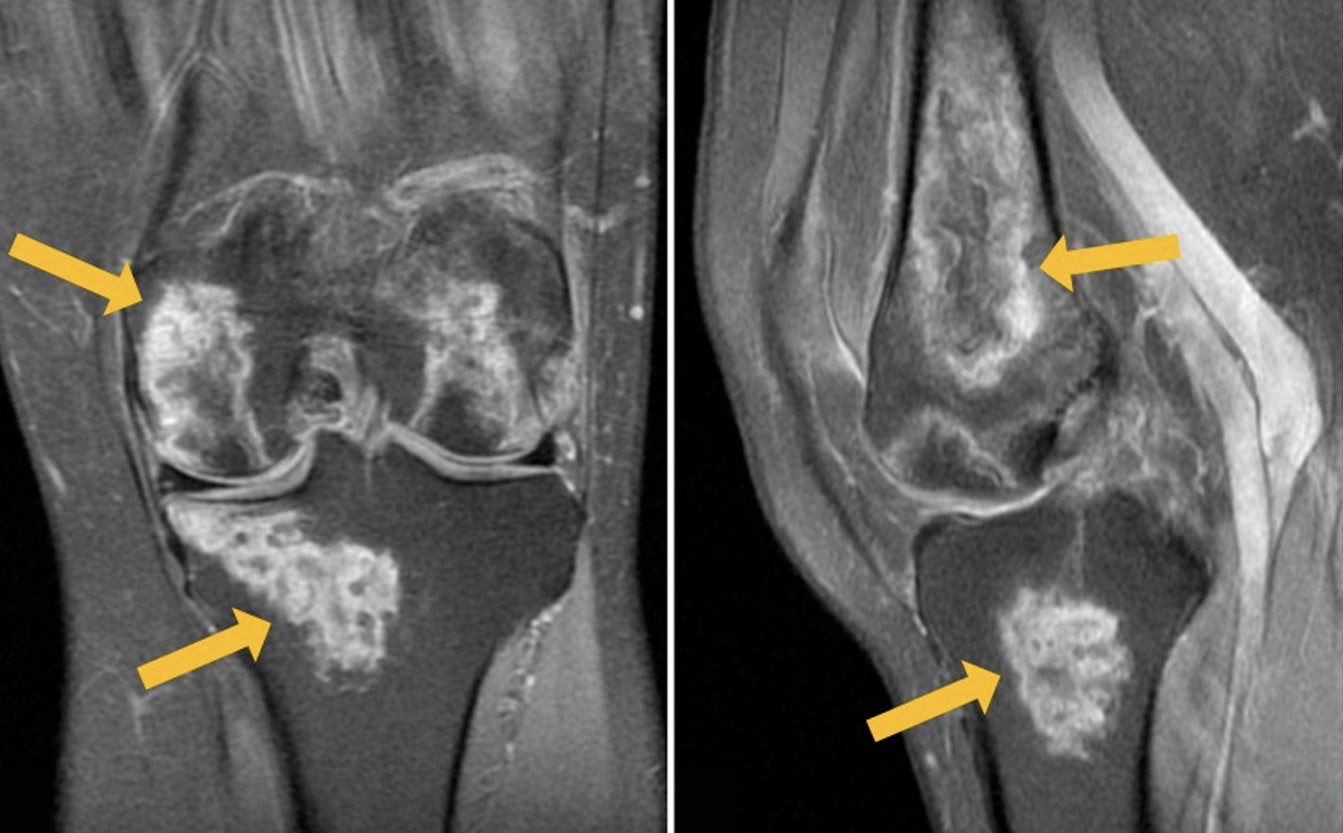

The development of bony avascular necrosis induced by glucocorticoid treatment of COVID-19 is a common adverse effect, with femoral head being the most commonly affected. Timely detection of avascular necrosis is important in the prevention of osteoarthrosis and other complications.

We present a clinical case of a 54-year-old patient hospitalized for novel coronavirus infection with complaints of severe pain in both knees 2 weeks after the disease onset. Magnetic resonance imaging revealed pronounced changes in both knees, corresponding to avascular necrosis. The results of conservative therapy, including non-steroidal anti-inflammatory drugs and bisphosphonate bone resorption inhibitors, produced a pronounced positive result. At follow-up examination 3 months later, there was no pain, but the knee joints still had slight restrictions of movement. Magnetic resonance imaging showed a significant decrease in the previously detected changes.

The side effects of glucocorticoids (impaired glucose tolerance, increased blood pressure, tachycardia, gastrointestinal erosive ulcers, sleep disorders, etc.) are widely known, but knee osteonecrosis caused by steroid intake rarely comes to the attention of clinicians. This clinical case emphasizes the complex nature of osteonecrosis pathogenesis and demonstrates a wide range of complications in corticosteroid therapy.